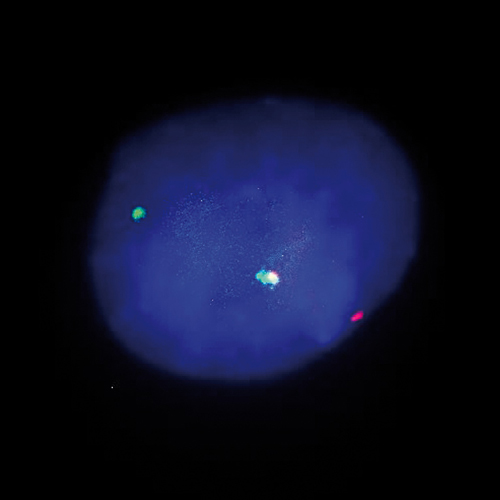

TFE3 (Xp11) Break probe hybridized to renal cell carcinoma showing a translocation at Xp11 (1RG1R1G). Image kindly provided by Dr. Desangles, Paris.

Abnormalities of Xp11.2 region have often been observed in papillary renal cell carcinomas and are sometimes the sole cytogenetic abnormality present. The transcription factor binding to IGHM enhancer 3 (TFE3) gene, which encodes a member of the helix-loop-helix family of transcription factors, is located in this critical region and can be fused to various other chromosomal regions by translocation. Known fusion partners are NONO (Xq12), PRCC (1q21), SFPQ (1p34), CLTC (17q23) and ASPSCR1 (17q25). The TFE3 (Xp11) Break probe is optimized to detect translocations involving the TFE3 gene region at Xp11.2 in a dual-color, break assay.